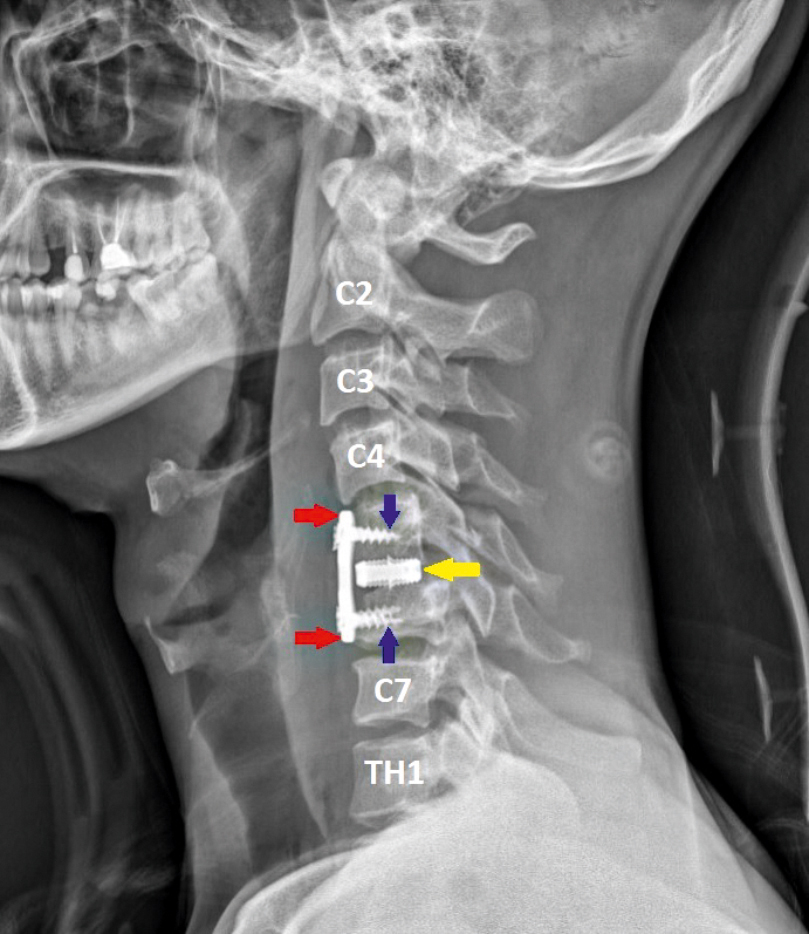

Врачи обнаружили множественные переломы и вывих пятого позвонка, перелом шестого позвонка, а также разрыв одного из межпозвонковых дисков, что привело к образованию грыжи, сдавливающей спинной мозг.

Титановая пластина

Нейрохирурги Пётр Галкин и Михаил Ветров разработали план операции. При помощи операционного микроскопа через небольшой разрез они удалили травматическую грыжу диска, затем под рентгеноконтролем успешно вправили вывих и зафиксировали позвонки при помощи титанового кейджа и пластины. «На следующие сутки после операции пациента перевели из реанимации к нам, в нейрохирургическое отделение. Шейный отдел позвоночника зафиксировали при помощи жёсткого воротника и в тот же день разрешили пациенту вставать и ходить. На третий день при контрольном обследовании мы убедились, что все функции организма удалось сохранить, имплант надёжно фиксирован, шов отлично затягивается. Пациент быстро шёл на поправку и на 5-е сутки после операции был выписан для продолжения реабилитационного лечения по месту жительства», – рассказал заведующий нейрохирургическим отделением Владимир Сериков.